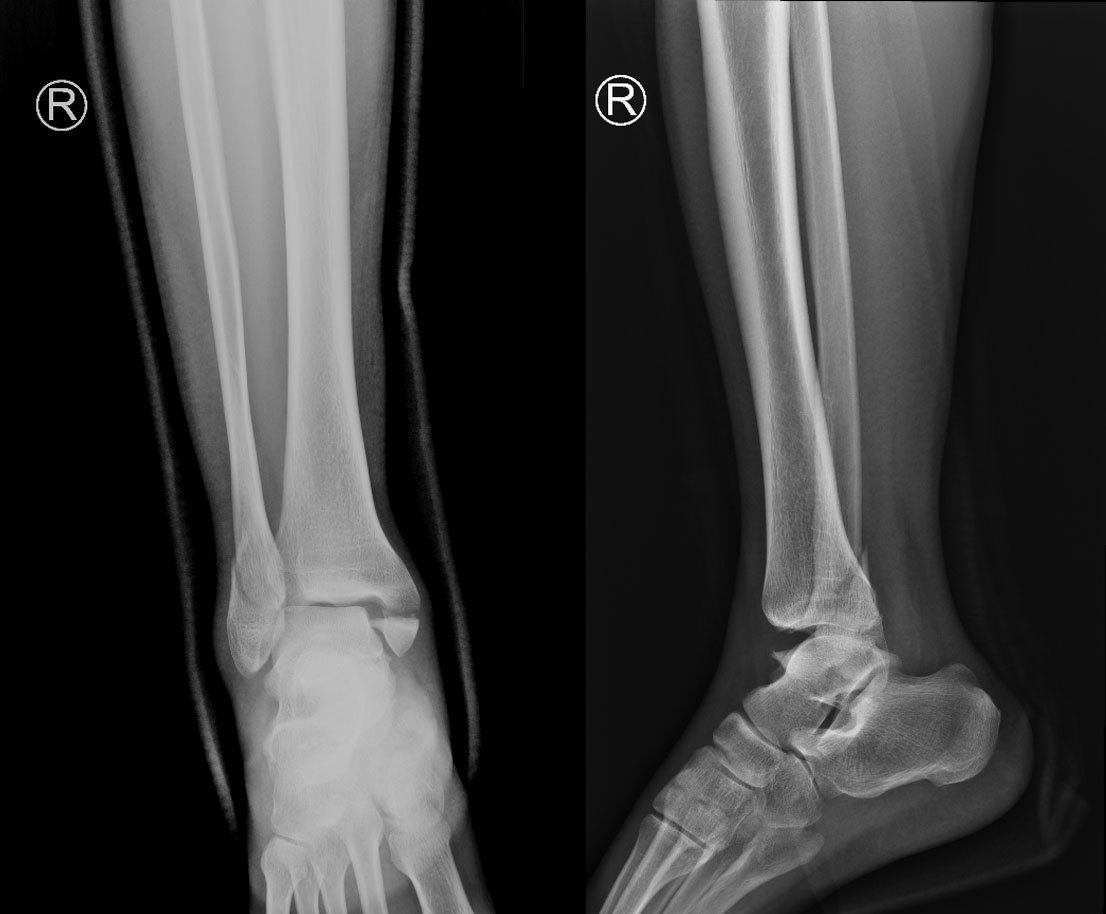

术前骨折照片